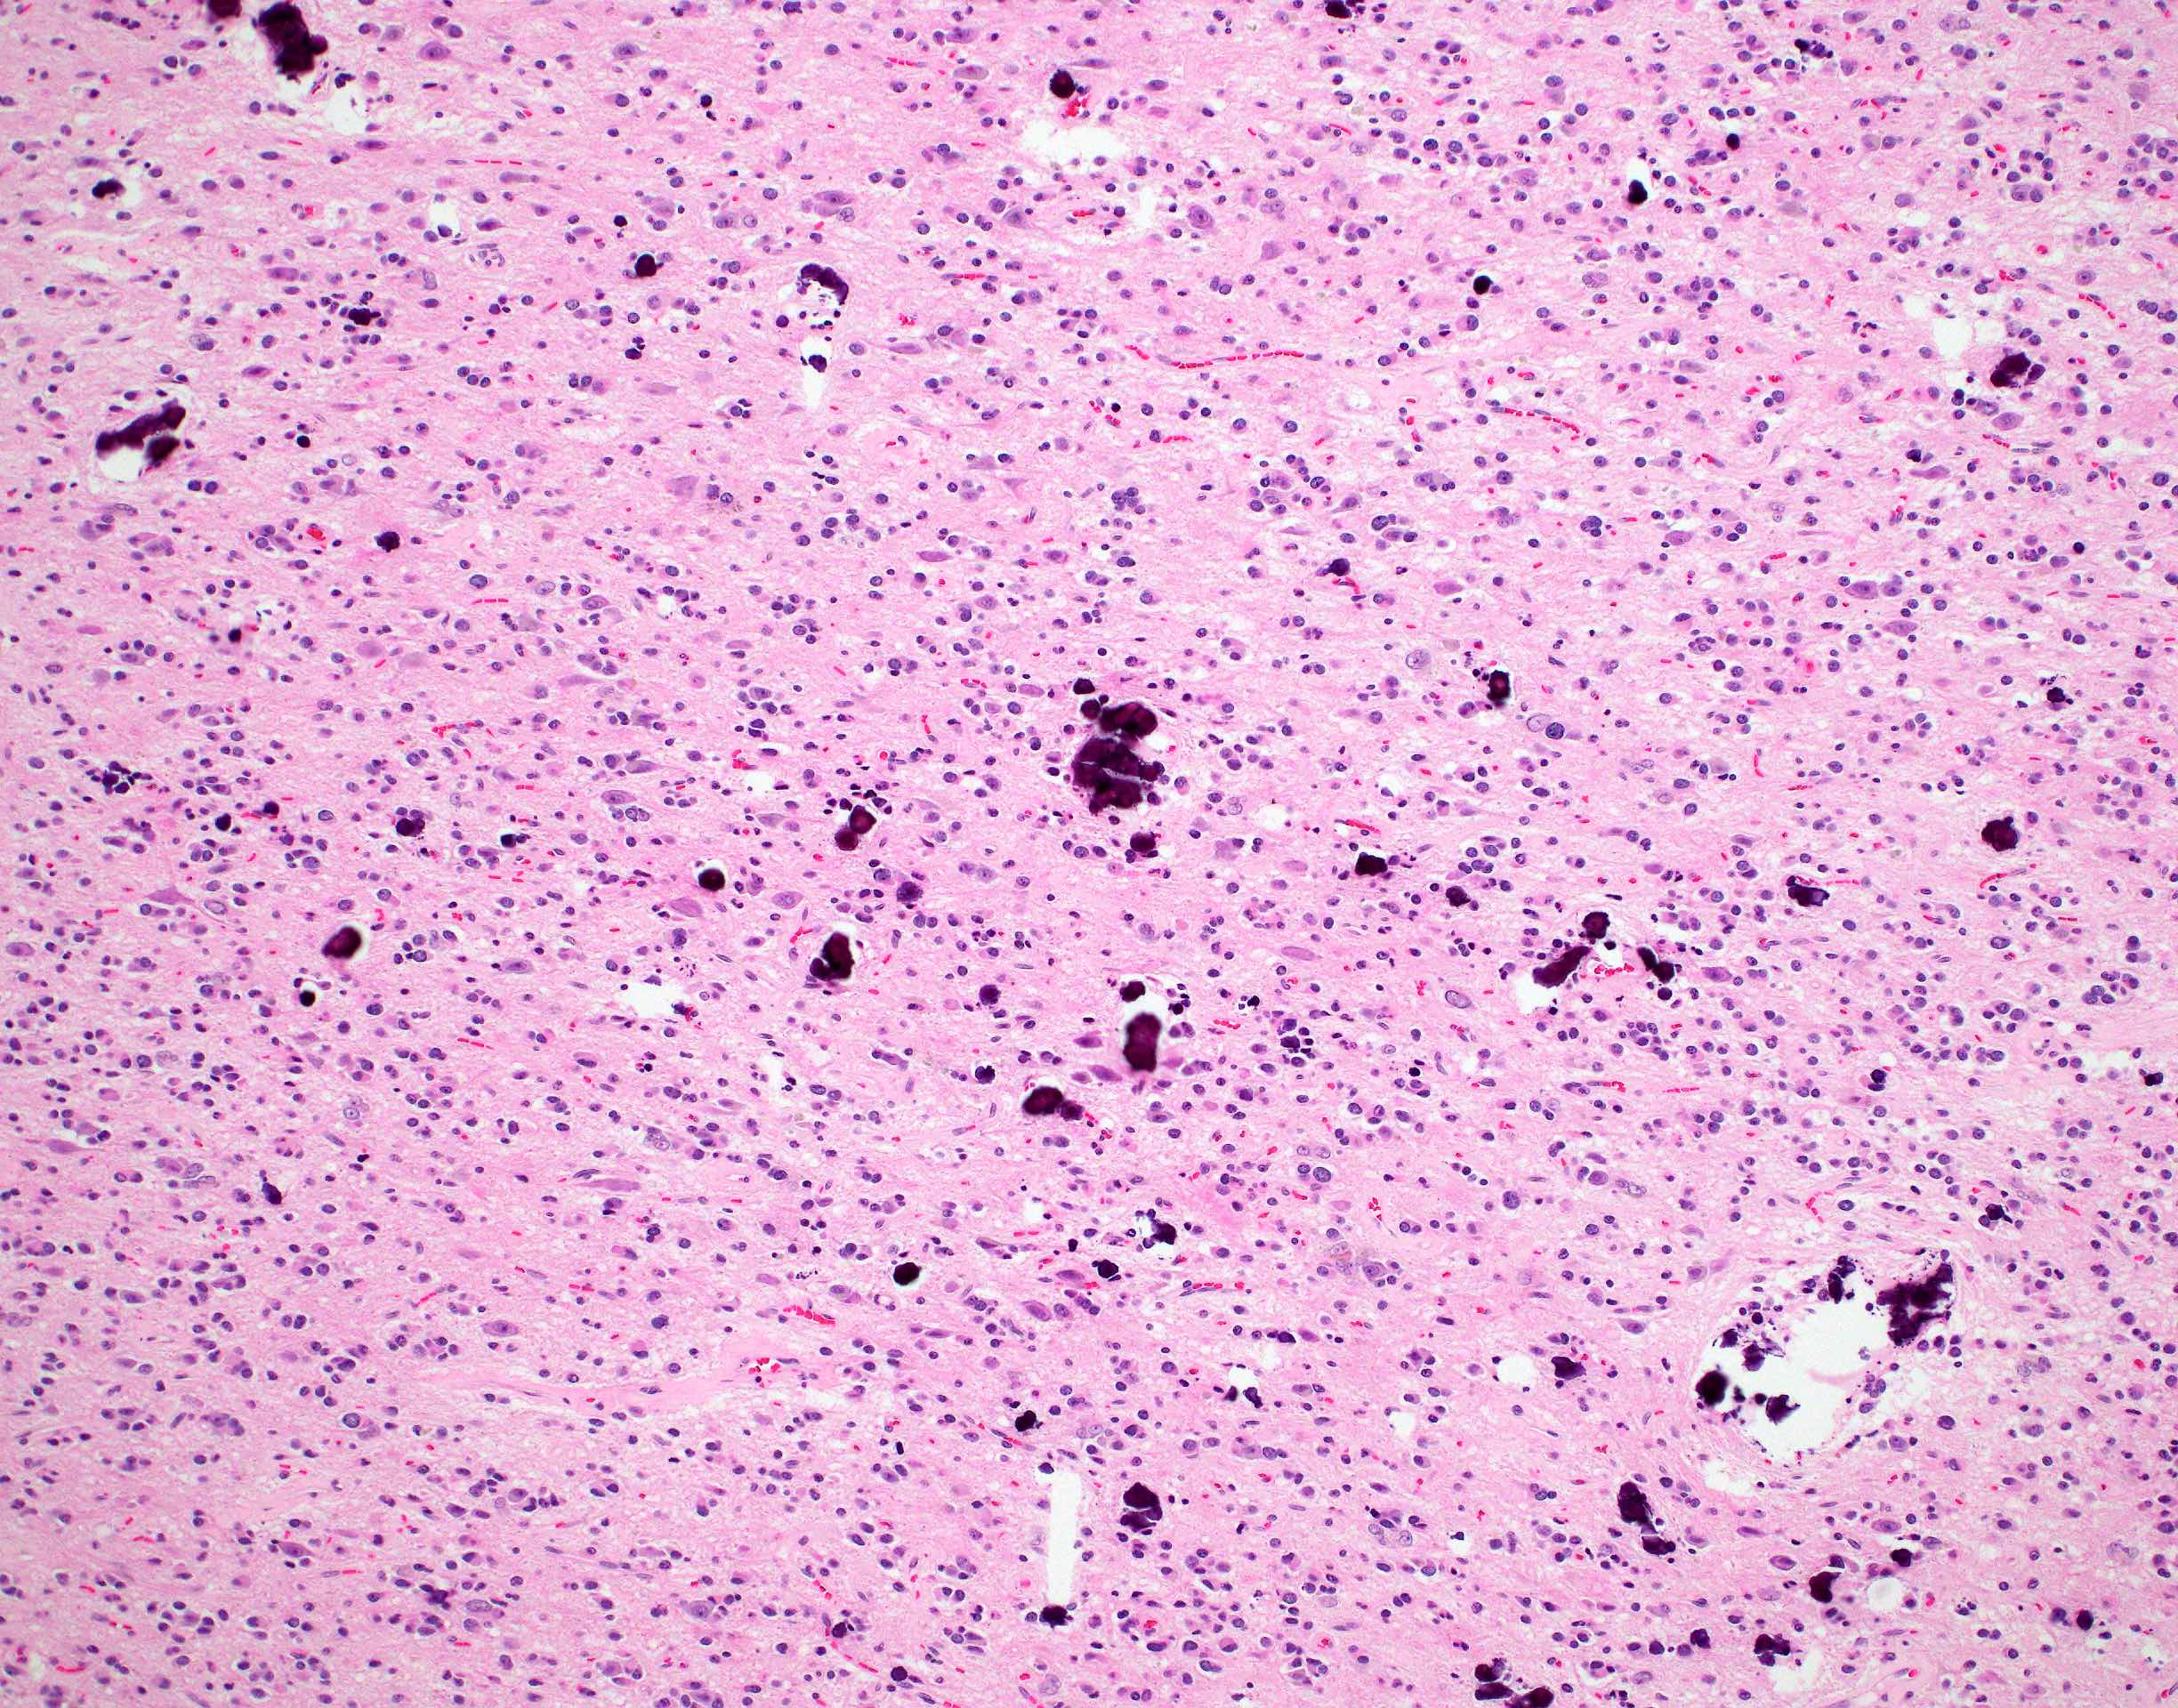

Microscopic (histologic) description

- Closely packed cells with small, round, monotonous nuclei (slightly larger than a normal oligodendrocyte)

- Perinuclear clearing (fried egg appearance)

- Formalin fixation artifact

- Will not be seen on frozen sections or smear preparations

- Network of thin walled, branching blood vessels (chicken wire vasculature)

- Microcalcifications (calcospherites) are characteristic

- Presence of perineural, perivascular or subpial aggregates of tumor cells (secondary structures of Scherer)

- Occasional mitoses and moderate nuclear atypia are still consistent with grade 2 designation (J Neuropathol Exp Neurol 2001;60:248)

- Not uncommon to find well differentiated / fibrillary astrocytic morphology (Acta Neuropathol 1984;64:265)

- Features of CNS WHO grade 3 oligodendroglioma:

- Presence of microvascular proliferation

- Presence of necrosis

- Presence of brisk mitotic activity

- Strict mitotic figure cutoffs do not currently exist; some authors suggest ≥ 6 mitoses per 10 high power fields for WHO grade 3 designation in tumors without necrosis or vascular proliferation (Neuro Oncol 2014;16:1244, Neuro Oncol 2016;18:888)

Microscopic (histologic) images

Contributed by Jared T. Ahrendsen, M.D., Ph.D. and John DeWitt, M.D., Ph.D.